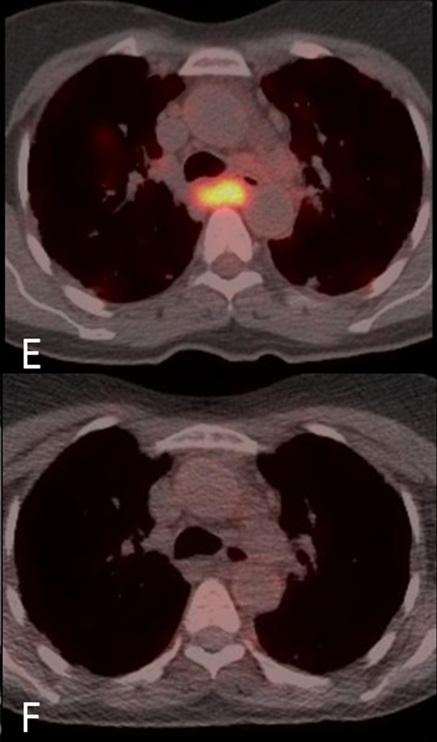

In this proof of concept study, Dr Stephen Jolles and colleagues from the University Hospital of Wales used an imaging technique called FDG PET-CT to simultaneously assess anatomical structure and metabolic activity in a patient with GLILD. FDG PET-CT imaging allows the detailed anatomical structure obtained by a CT scan to be overlaid and combined with PET images of rates of labelled glucose uptake into cells within the tissues; the clinical utility of which has already been proven in oncological imaging. However, FDG PET-CT's use to assess inflammatory disease is an emerging field and this paper is the first time that this technique has been employed to assess both anatomical and metabolic extent of the disease and to assess treatment response in the setting of GLILD.

The images (supplied) show that FDG PET-CT provides new insights into GLILD, showing widespread, high levels of metabolic activity not restricted to the lungs but affecting lymph nodes (even when these are normal in size) throughout the body before treatment. After treatment, clear improvements in both anatomical and functional activity can be observed. The combined FDG PET-CT demonstrates that GLILD is only the pulmonary facet of a highly metabolically active multisystem disease. The very high levels of metabolic activity may have implications for the development of autoimmunity and malignancy, both of which occur at higher frequency in patients with GLILD.

This study is the first time that the imaging technique, FDG PET-CT, has been used to assess the combined lung structure and metabolic activity in a patient with GLILD before and after treatment. The images are striking and enlightening in that they reveal the highly metabolically active multi-systemic nature of the disease. It remains to me amazing the ability of this technique to overlay structure with metabolic functional activity in this way."